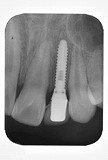

歯列矯正 歯肉形態修正手術 インプラント メタルボンドを併用した症例です。

この治療では1本の歯も削ったり、抜いたりはしていません。

- 先天的に上顎側歯列が欠如している患者さんです。

- はじめに矯正治療を行い、本来歯があるべき位置に矯正して、インプラント手術のためのスペースを確保しました。

- 矯正治療終了後に歯肉の形態修正手術を行いました。

- 本来の側切歯部分にインプラント埋入

- メタルボンドにて修復